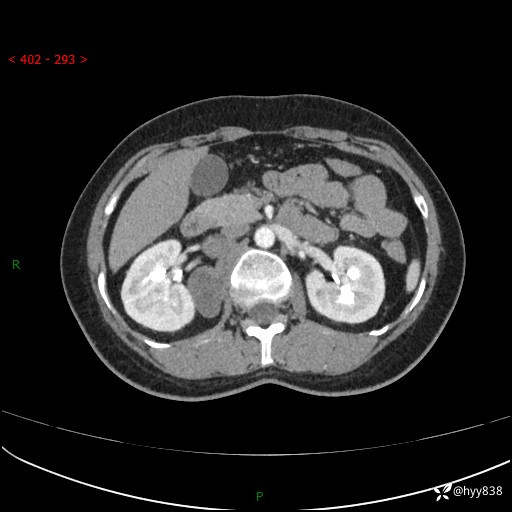

简要病史:患者于1天前因体检发现右旁肾占位,无肉眼血尿,无畏寒发热,无咳嗽咳痰,无腰腹部疼痛不适,无尿频尿急症状,起病来,患者未行特殊治疗,为求进一步诊治,门诊以"右侧腹膜后肿物"收治入院。 发病来患者精神、饮食、睡眠良好,小便如上,大便正常,体重无明显变化。

辅助检查:CT

临床诊断:腹膜后肿物

上腹部CT增强(动脉期+实质期)(外院平扫)